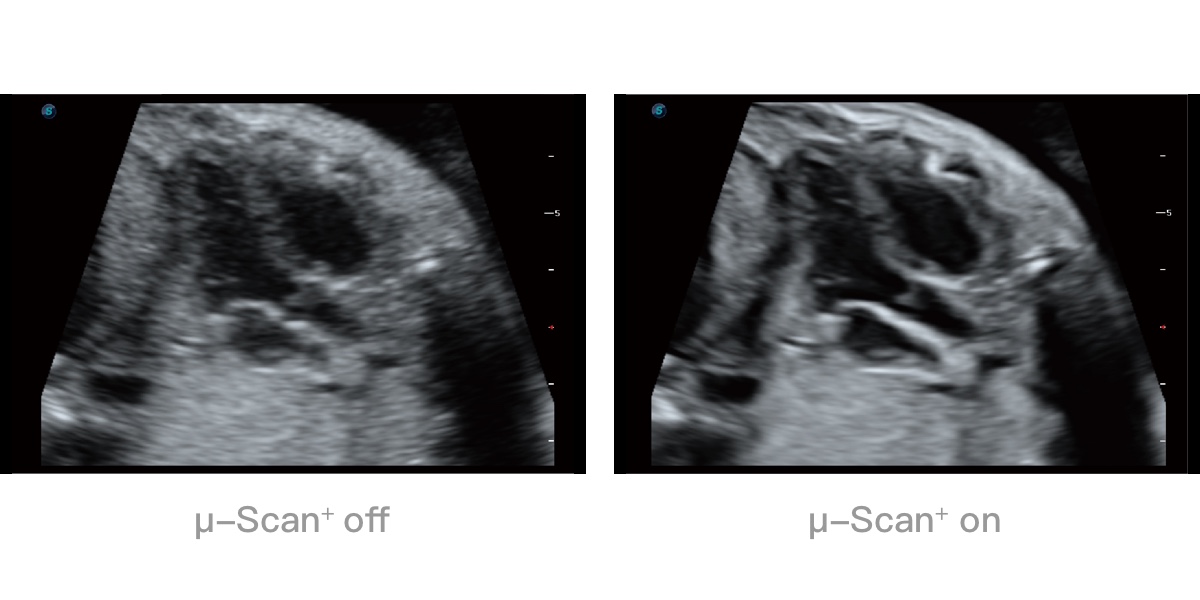

微米成像技术提升了对组织斑点噪声信号的抑制能力,并进一步强化边界信息,从而获得清晰图像。